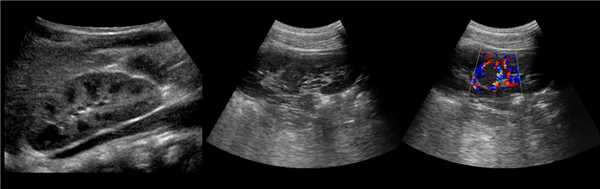

Рисунок. На УЗИ синус почки разделяет полная паренхиматозная перемычка (1, 2). В таких случаях разграничить удвоение почки от гипертрофии колонны Бертини поможет экскреторная урография. Удвоенная почка покрыта общей фиброзной капсулой. Полное удвоение предполагает наличие двух лоханок, двух мочеточников и двух сосудистых пучков. Неполноудвоенная почка (3) питается одним сосудистым пучком, мочеточник может быть удвоен вверху и впадать в мочевой пузырь одним или двумя устьями. Удвоение ЧЛК и мочеточников — фактор риска развития патологии (пиелонефрита, гидронефроза и др.).

Рисунок. Независимо от наполнения мочевого пузыря на УЗИ видно лоханку смешанного (1, 2) и экстраренального (3) расположения.